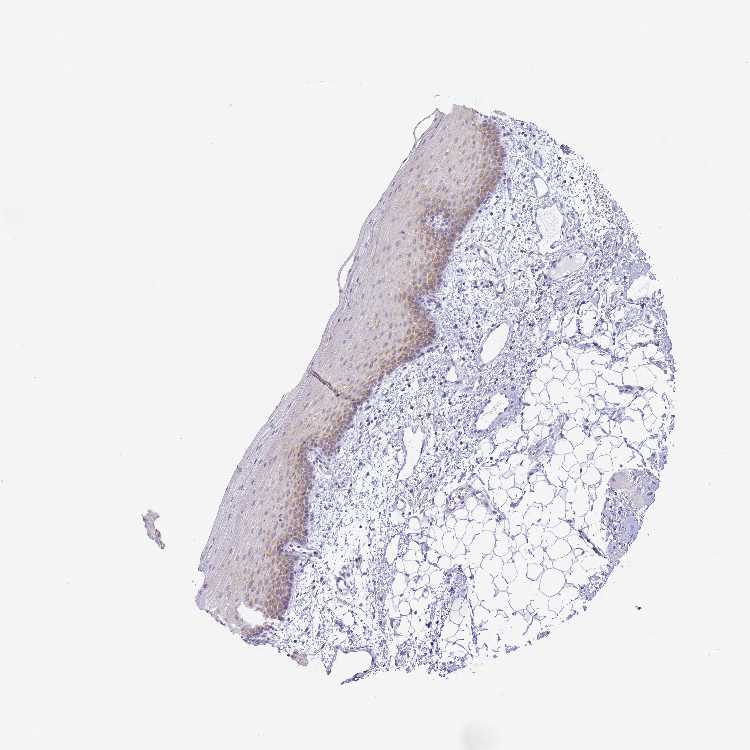

TISSUE PRIMARY DATA ORAL MUCOSA Show tissue menu

ORAL MUCOSA - Antibody stainingi

Antibody staining in the annotated cell types in the current human tissue is reported as not detected, low, medium, or high, based on conventional immunohistochemistry profiling in selected tissues. This score is based on the combination of the staining intensity and fraction of stained cells.

Each image is clickable and will lead to virtual microscopy that enables deeper exploration of all samples and also displays staining intensity scores, fraction scores and subcellular localization as well as patient and tissue information for each sample.

Antibody HPA042455Antibody HPA043579Antibody HPA049348Antibody CAB002491Antibody CAB016271

Squamous epithelial cells Not detectedMediumNot detectedNot detectedNot detected